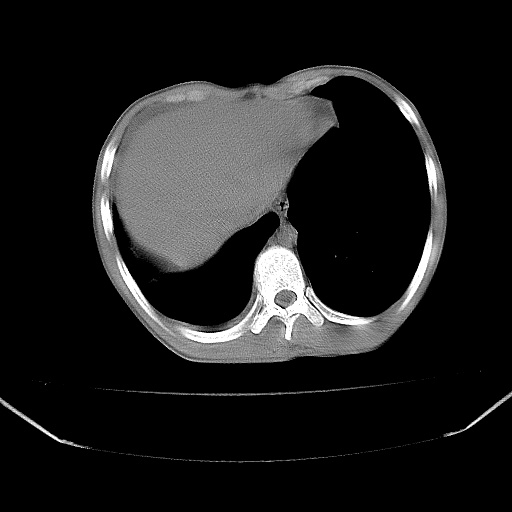

以下是引用zjzjr在2008-7-20 12:57:00的发言:[br]考虑为生殖源性肿瘤(内胚窦瘤),侵袭性胸腺瘤可能性大;右侧少量胸腔积液。

以下是引用xinliheng001在2008-7-20 21:17:00的发言:[br]右纵隔巨大分叶状软组织均质密度肿块,右上肺叶受压明显,纵隔右移、胸膜受累有少量积液和结节样增厚。应增强扫描一定会有更具诊断价值的信息。

以下是引用xinliheng001在2008-7-20 21:17:00的发言:[br]右纵隔巨大分叶状软组织均质密度肿块,右上肺叶受压明显,纵隔右移、胸膜受累有少量积液和结节样增厚。应增强扫描一定会有更具诊断价值的信息。